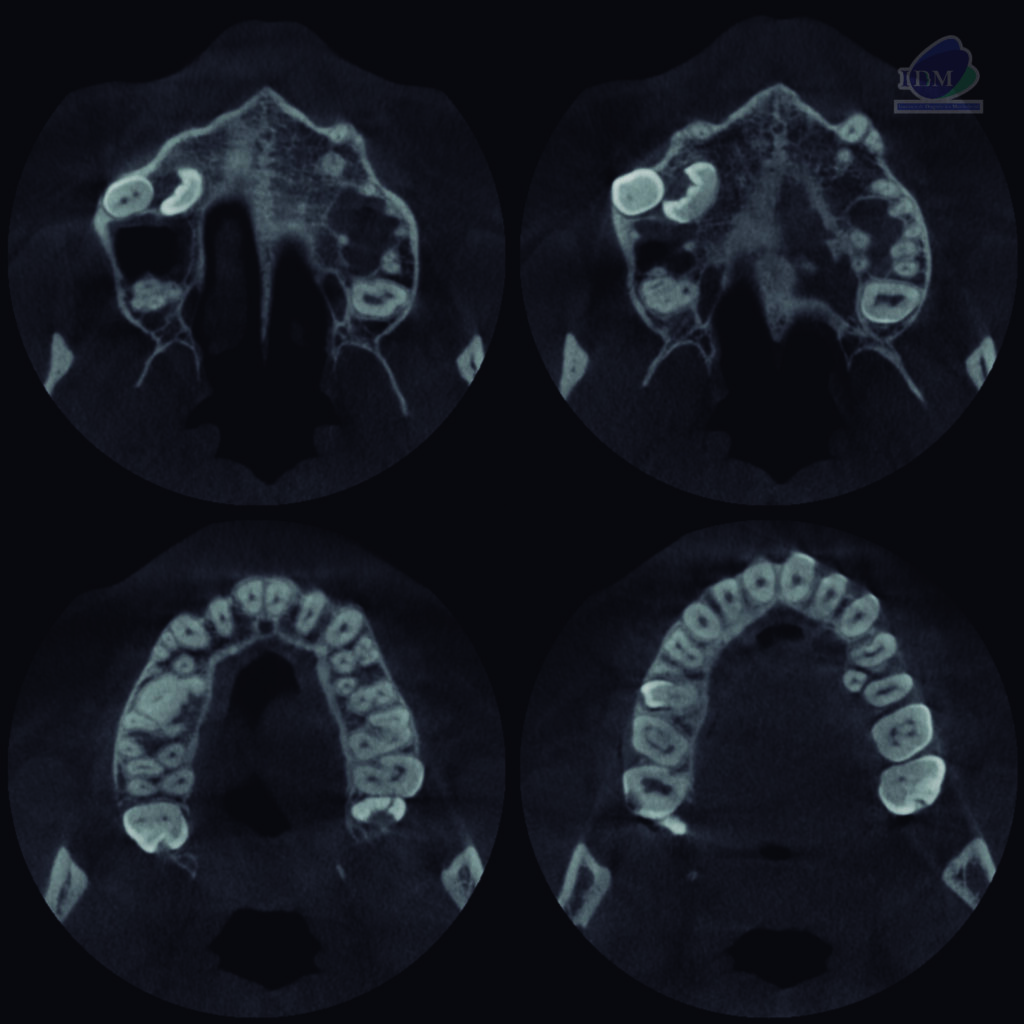

A la evaluación de la tomografía volumétrica (CBCT) en los cortes axiales (Figura 2) y transaxiales (Figura 3), se aprecia pieza supernumeraria 1 localizada entre pieza 55 y pieza supernumeraria 2. Imagen hiperdensa (pieza supernumeraria 2), de limites definidos y forma irregular, que se extiende en sentido cefálico caudal desde piso de seno maxilar hasta pieza supernumeraria 1, que ocasiona el desplazamiento de pieza 15 comprometiendo piso de seno maxilar.

CORTES AXIALES